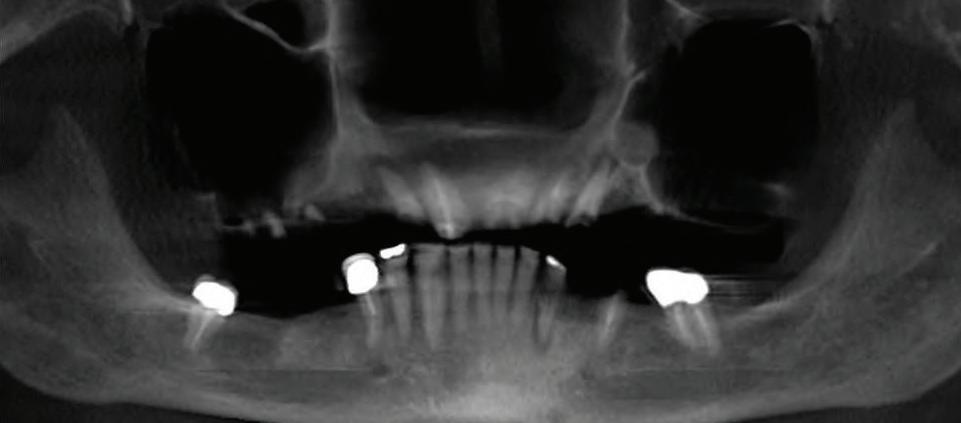

22 | Bariatric Surgery: Dr.’s Cover the Insurance Coverage Option | By Etwar McBean, MD, FACS 24 | All-On-Four Dental Implants | Submitted By Sivakumar Sreenivasan, DMD, MDS

Can just four implants replace all of the teeth on the top or the bottom of your mouth? Thanks to advances in dental implant technology, that answer is a resounding yes.

Tooth loss is extremely common among adults, especially as we age. Rather than living with the discomfort and hassles of dentures, many people are opting for what is called “all-onfour” dental implant restoration.

An implant is a small titanium

screw that fits inside your jawbone and replaces the root-part of a missing tooth. Minor surgery is required to insert the implants. Once the implant is in place, a crown is attached to give you a highly realistic-looking and functional prosthetic tooth.

You do not need a dental implant for each and every one of your missing teeth. All you need is four precisely placed implants on the top of your mouth, and four on the bottom, to restore your full smile. That’s the beauty of the all-on-four. And because the implant is made of titanium, it has the unique ability to fuse to living bone and function as part of it. So eventually, the dental implant becomes part of the jawbone and serves as a strong, longlasting foundation for your new teeth.

Besides ensuring that your implants are permanently fixed in place, this bone fusion has another important benefit: it prevents future bone loss in the jaw. This helps to maintain a more youthful facial structure – and better

Please see “All-On-Four,” page 62